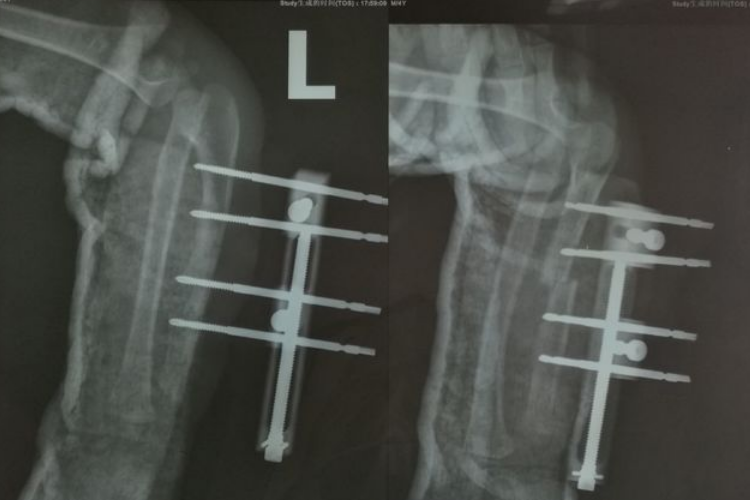

骨痂是骨延长愈合过程中新形成的连接骨折两端的骨组织,骨延长骨痂生长过程中先形成纤维骨痂再形成骨性骨痂。

在骨延长术后两周左右,由于早期大量的纤维细胞、成骨细胞等增殖活动,分泌出大量基质、成纤维细胞和成骨细胞,形成纤维骨痂,可包围并固定骨两端。

纤维骨痂形成后,成骨细胞活跃,分泌出均质透明的类骨基质,继之形成类骨组织,而后钙质在类骨基质间不断沉积形成骨组织,此时骨痂称为骨性骨痂。